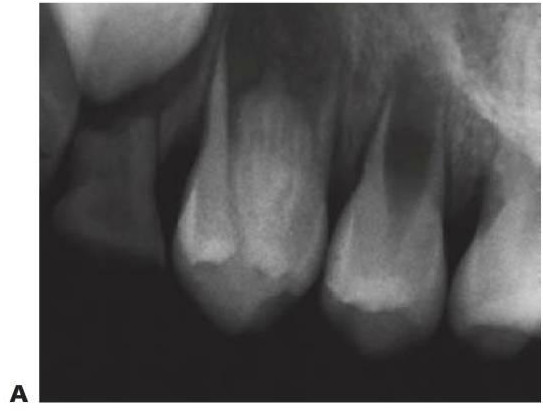

Dens invaginatus

Los incisivos laterales maxilares pueden presentar una invaginación (consecuencia del desarrollo) de la fosa cingular que presenta con frecuencia tan sólo una fina barrera de tejido duro que separa la cavidad oral y la pulpa. Suele producirse una necrosis pulpar poco después de la erupción del diente afectado y puede ocasionar un absceso o una celulitis en la fosa canina. Esta anomalía puede aparecer en otros dientes, como los incisivos centrales y caninos superiores (figs. 9 19,9.20).

Terminología alternativa

Odontoma invaginado, dens in dente (utilizado para describir la variante más extrema, pero no es un nombre apropiado), odontoma dilatado.

Tratamiento

- Si ha erupcionado de forma reciente, se puede prevenir mediante el sellado de las fisuras de la superficie palatina.

- Si hay caries, colocar una resina de composite tras un grabado ácido.

- Si el diente es asintomático y la morfología del conducto radicular resulta favorable, se puede llevar a cabo el tratamiento endodóncico.

- Si la anatomía interna es compleja y el conducto radicular no resulta accesible, en caso de infección se procederá a la extracción del diente. Se debe analizar de forma exhaustiva la presencia de esta anomalía durante la planificación del tratamiento ortodóncico.